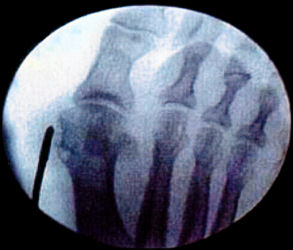

Osteotomies in the 1st metatarsal can be distal metatarsal osteotomy such as the ReverdinIsham with a medial wedge respecting the lateral cortex and performing an Osteoclasis to correct the PASA and we can also perform a modification of this osteotomy by completing it and sliding the metatarsal head laterally thereby increasing the relative closure of the 1st intermetatarsal angle. Next we can do a proximal metatarsal osteotomy performed with a wedge osteotomy proximal laterally to close the intermetatarsal angle. Another procedure that we can perform is an abductor release which is a Modified McBride. The next procedure we can do is also an osteotomy of the base of the proximal phalanx (Akin).

Hallux valgus in a young patient with intermetatarsal angle less than 20 degrees and PASA more than 8 degrees. The treatment would be exostectomy, osteotomy distal, ex., Reverdin Isham, tenotomy of the abductor and if the DASA is elevated then an osteotomy at the base of the proximal phalanx (Akin).

If we have a patient that is young with a intermetatarsal angle more than 20 degrees, PASA more than 8 degrees the protocol would be exostectomy, tenotomy of the abductor, osteotomy distal Reverdin Isham (and metatarsal base osteotomy) and with an elevated DASA we would do an Akin procedure at the base of the proximal phalanx.

If the patient is more than 45 or 50 years and has an intermetatarsal angle less than 20 degrees or greater than 20 degrees if the patient is sedentary, we would do an exostectomy, an osteotomy of the distal metatarsal, ex., Reverdin Isham, tenotomy of the abductor, and if the DASA is elevated then we would do an Akin osteotomy.

If the patient is 45 to 50 years of age and is an athlete or is very active and has an intermetatarsal angle greater than 20 degrees, we would perform an exostectomy, an osteotomy of the distal metatarsal to correct the PASA, ex., Reverdin Isham, an osteotomy at the base of the 1st metatarsal, abductor tendon release and if the DASA is elevated we would do an Akin procedure.

If the patient is elderly and has an intermetatarsal angle less than 20 degrees, we would perform an exostectomy, an osteotomy of the distal phalanx of the 1st metatarsal Reverdin Isham, an abductor tenotomy, and if the DASA is elevated then we would do an osteotomy of the proximal phalanx, an Akin procedure.

If we have an elderly patient with intermetatarsal angle greater than 20 degrees, we would do an exostectomy, an abductor tenotomy, an osteotomy of the 1st metatarsal distal and after a Reverdin Isham Modified and if the DASA is elevated then an Akin procedure would be performed.